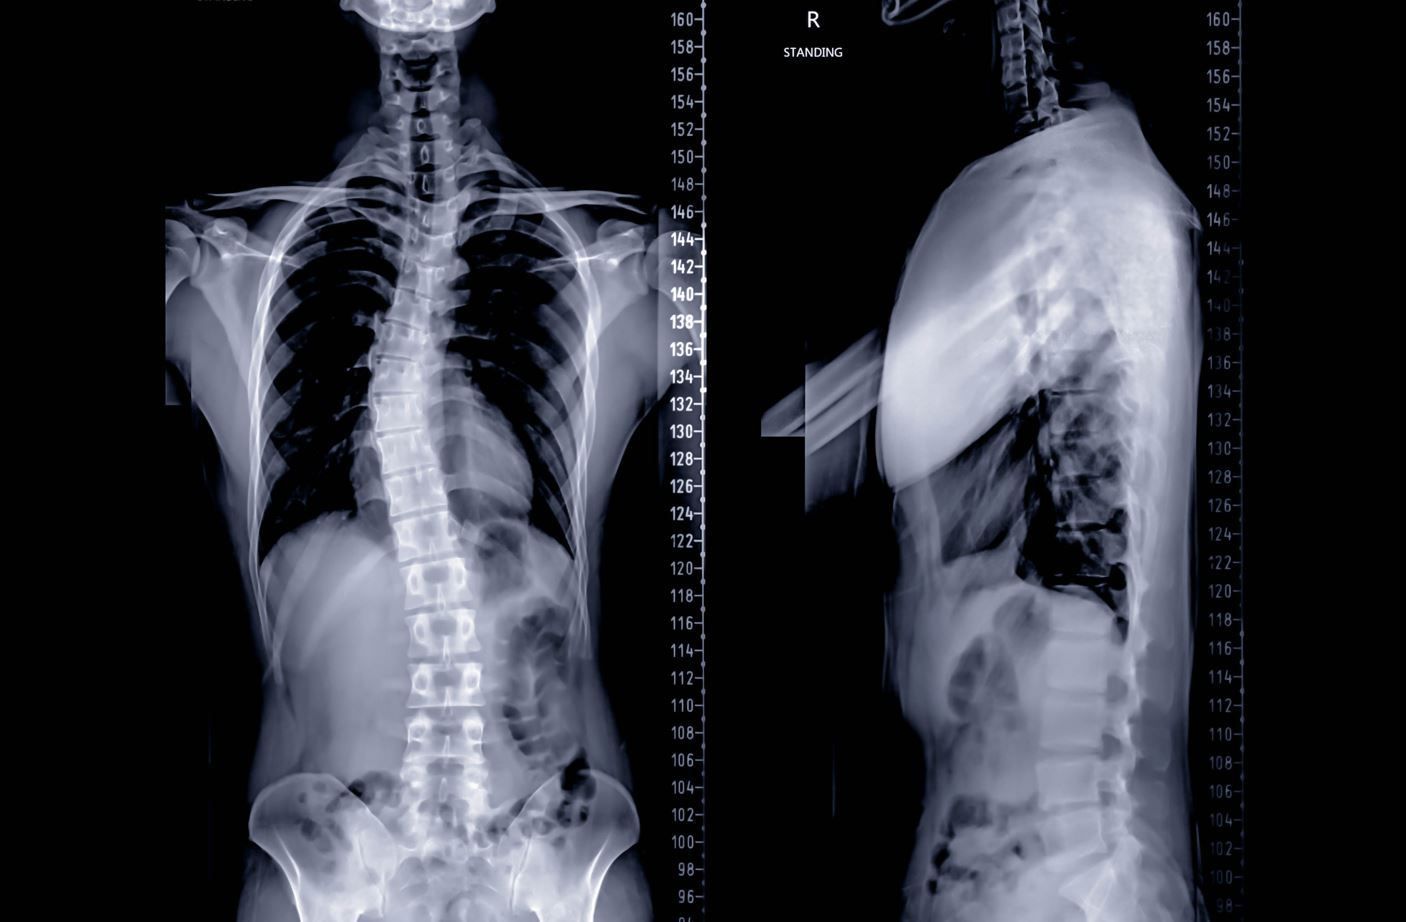

Scoliosis is a common cause of malalignment syndrome.

• Genetics: Genetic conditions such as scoliosis or flat feet can create poor posture